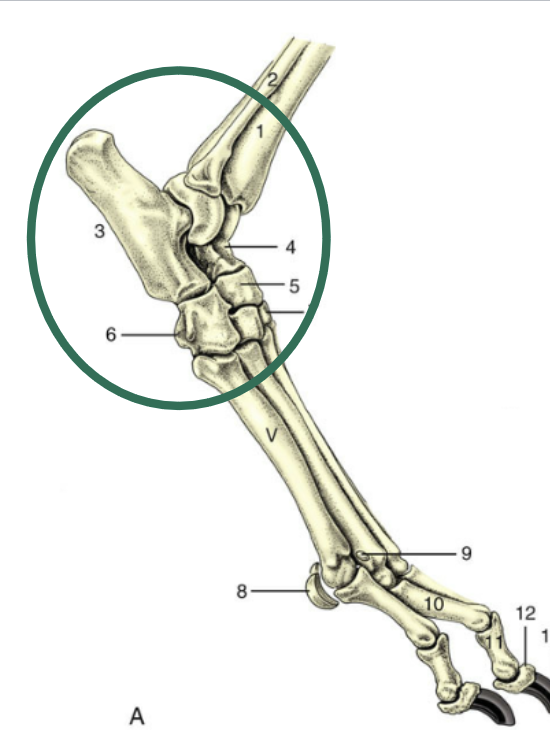

Which joint is found here?

Glenohumeral Joint

Which joint is #1?

Humeroradioulnar joint

Which joint is #2?

Carpus